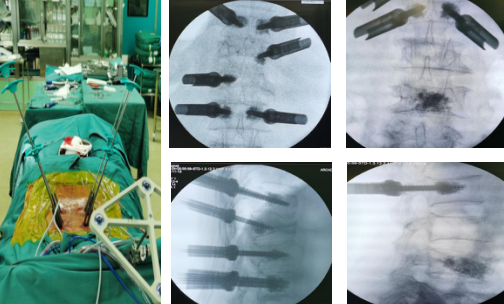

在天玑机器人的精确定位下,手术团队沿着套筒钻入导针,确认位置无误后,再沿导针拧入单平面骨水泥螺钉,注入骨水泥;待骨水泥凝固,上连接棒,撑开,实施减压手术;手术在骨科机器人的精准导航下,顺利完成,实现了手术的微创化、精准化、智能化。

定位,标记,扫描传送规划,钻入导针

拧入单平面骨水泥螺钉,注入骨水泥

“这台手术,如果采用传统手术方式,需要切开近20厘米的切口,有了‘天玑’机器人的辅助,只在患者腰椎两侧各切开几个1厘米左右的切口,利用天玑强大的光学追踪系统和灵活稳定的机械臂进行操作,精准度达到0.8毫米,手术用时也缩短了三分之一。”孟磊医生说,由于伤口小、出血量少,患者术后恢复时间也大大缩短。

待骨水泥凝固,上连接棒,撑开,+减压手术